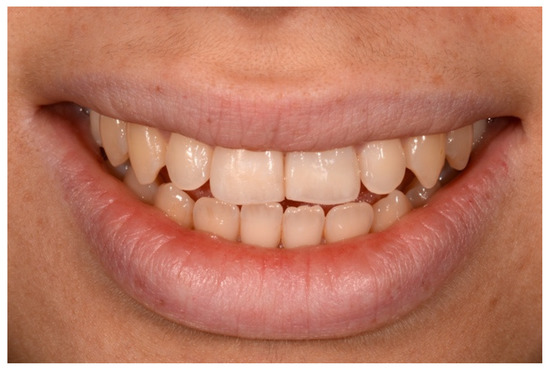

2. Case Presentation